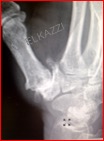

Le traitement chirurgical (photo) doit être envisagé en cas d’échec du traitement orthopédique traditionnel ; il repose sur deux axes à savoir l’arthroplastie prothétique (prothèse totale) et l’arthroplastie-résection (Trapèzectomie). Le choix de l’une ou l’autre technique dépend du stade radiologique de l’arthrose, de l’âge du patient et de son activité.

La chirurgie donne de bons résultats sur la douleur et la mobilité. Les suites opératoires sont marquées par une immobilisation plâtrée de 2 semaines pour les arthroplastie-prothétiques et de 6 semaines pour les trapèzectomies. Une rééducation de courte durée suivra le retrait du plâtre et rapidement les patients retrouvent leurs autonomies.